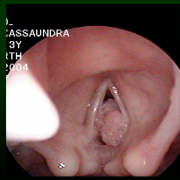

- 75% diagnosed by 5 years of age with most common presentation in 2- to 5-year-olds. Classic triad of first born to young, sexually active mother delivered vaginally. Caused by HPV 6 and 11. Recurrences due to latent infection in surrounding tissues with predilection for areas of stratified squamous epithelium and iatrogenic areas of squamous metaplasia.

- For recurrent respiratory papillomatosis, recognize the limitations of surgical debulking in the treatment of this disease caused by a latent viral infection.

- Understand the choices of surgical methods of debulking including:

- RRP: A 2-year-old girl presents to the emergency room with progressively increasing stridor with activity and persistent dysphonia. She is the first-born child of a then 17-year-old mother, delivered vaginally without problems in the delivery suite. Mom has had an abnormal pap smear but denies condylomata. The child has been labeled as “asthmatic” and has made several previous visits to the emergency department and was treated with bronchodilators. At the present time she is in mild distress with use of accessory muscles of respiration but no air hunger, cyanosis, or dyspnea. Her pulse oximetry reads 100% saturation.

- Probable laryngeal papillomatosis.

- Treatment requires visualization of larynx and biopsy if appropriate. In a 2-year-old with mild distress this is best accomplished in a controlled setting (the operating room [OR]) with appropriate equipment and personnel readily available. The child needs to be consented for airway endoscopy and possible removal of papillomas and the mother needs to be counseled regarding the recurrent nature of these lesions. The OR needs to be properly set up in advance and the OR team and anesthesia team, along with the surgeon, need to discuss the sequence of events and the equipment that will be utilized before the child enters the OR.